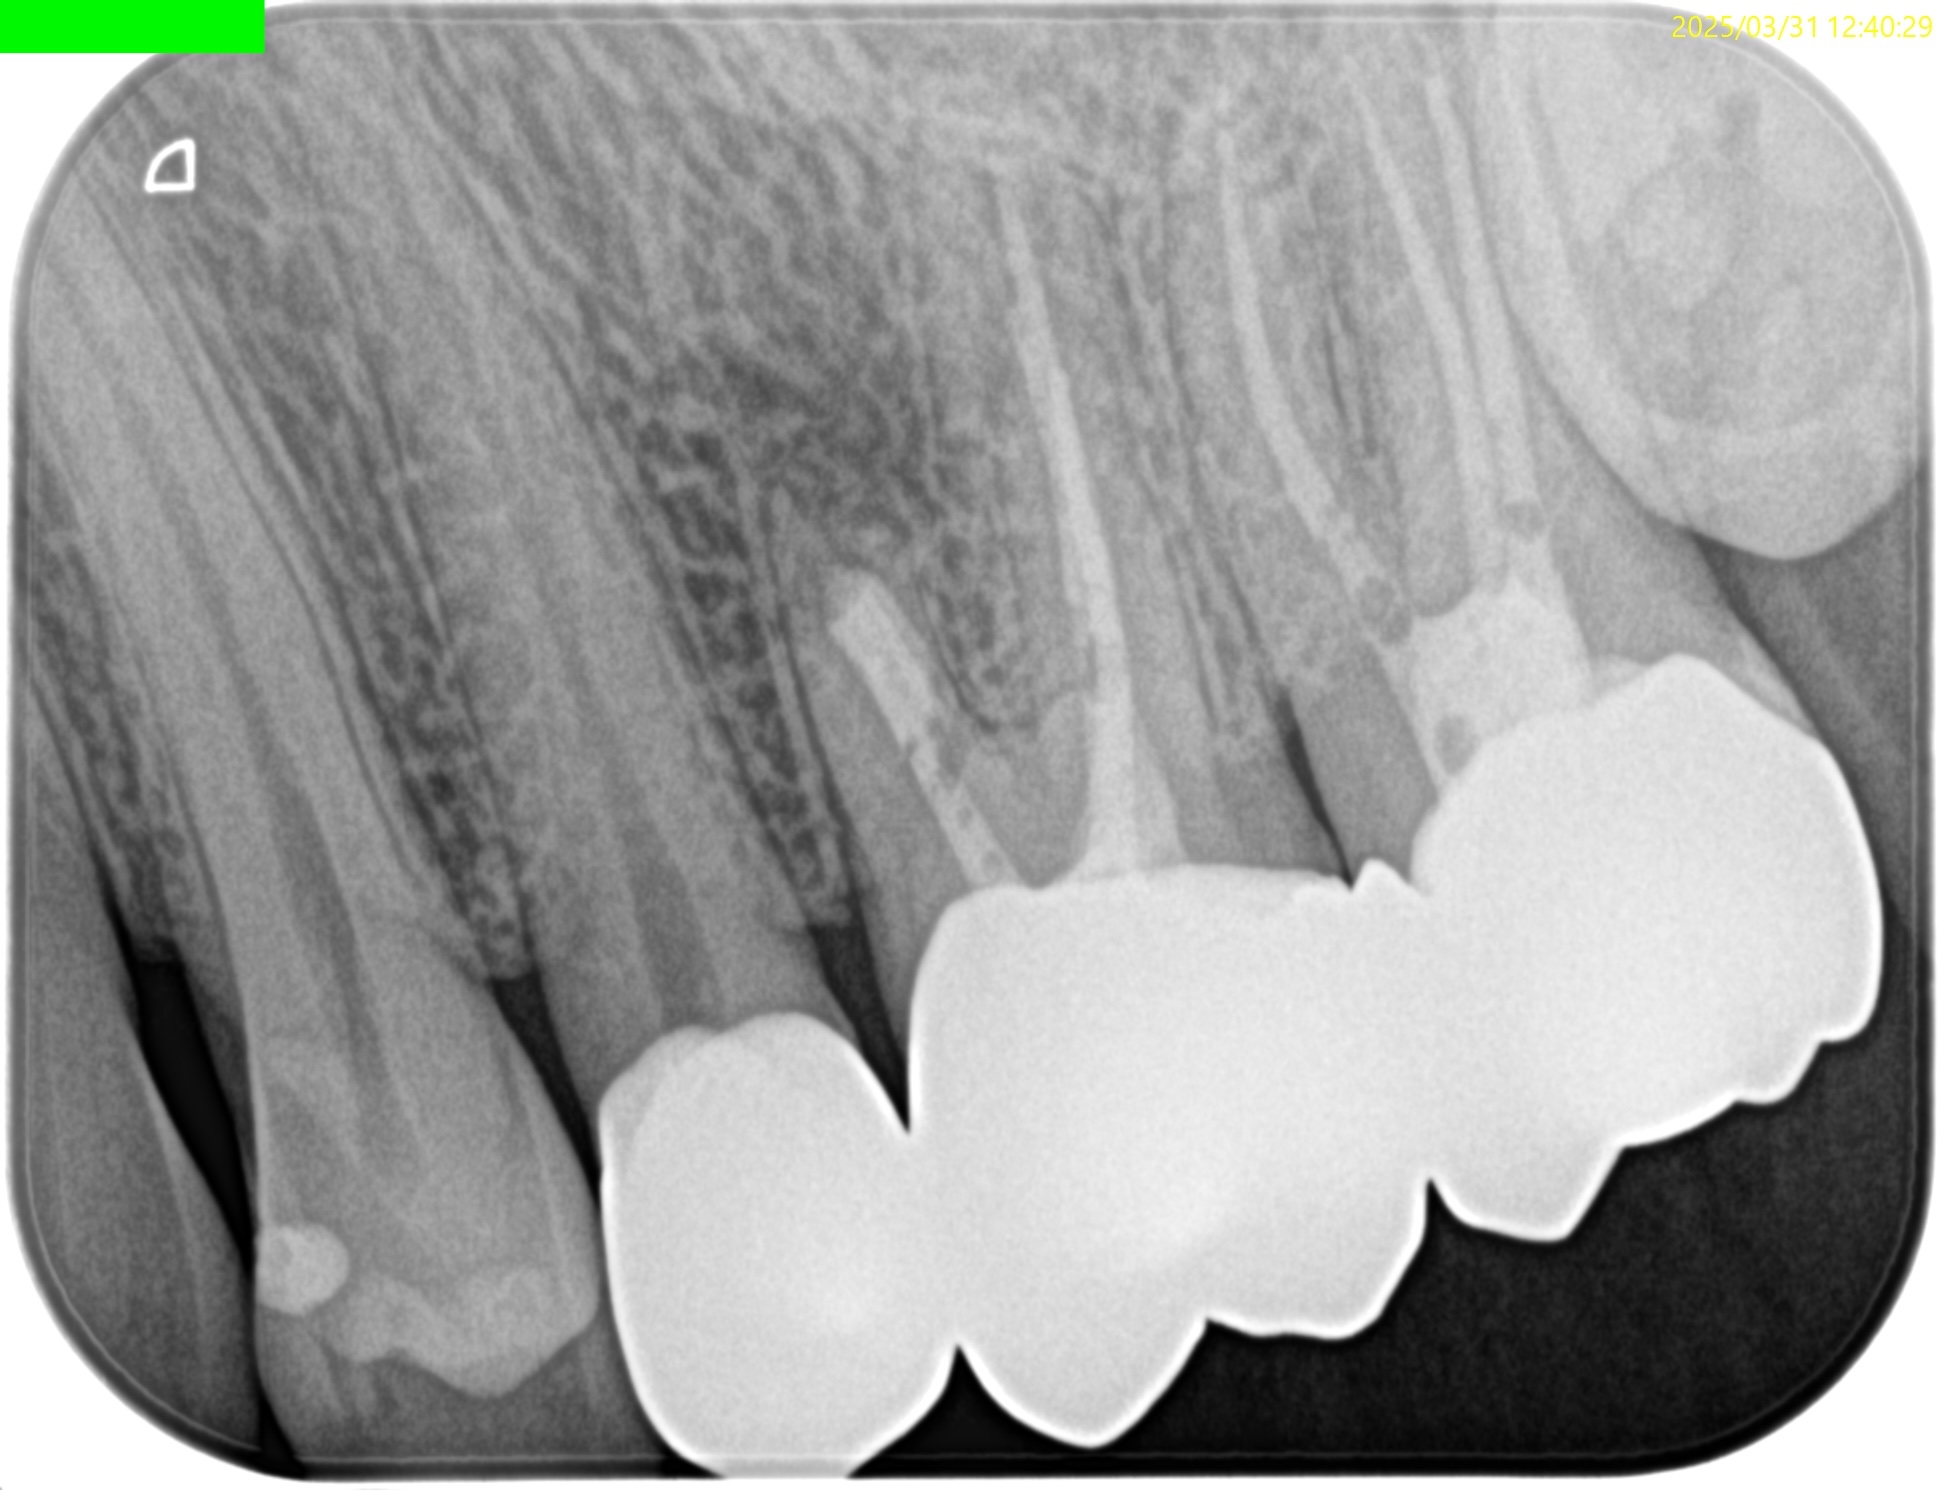

Pre-op Endo test(2025.3.31)

MB

DB

P

MBに大きな病変がある。DB,Pには病変はない。

これが検査での圧痛の原因だろう。